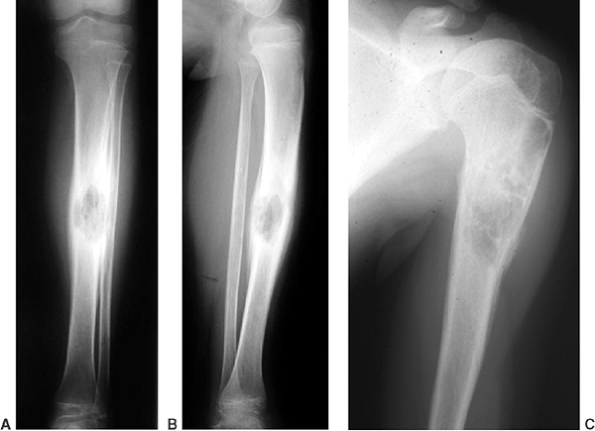

Figure 11.3

A 17-year-old boy with sickle cell disease presented with symptoms of a painful crisis in his leg. Plain radiographs of his tibia revealed no abnormalities. Failure to respond to hydration after 2 days, along with elevated peripheral white blood cell count and C-reactive protein, prompted investigation with magnetic resonance imaging. Sagittal T1-weighted images before (A) and after (B) gadolinium injection demonstrate heterogeneous enhancement throughout a large area of abnormal signal intensity in the marrow of the tibia. An intraosseous fluid collection can be seen (arrow). Axial T1-weighted (C) and T2-weighted (D) images without gadolinium demonstrate an extraosseous fluid collection (arrows) with surrounding edema. Operative corticotomy yielded purulent material. |